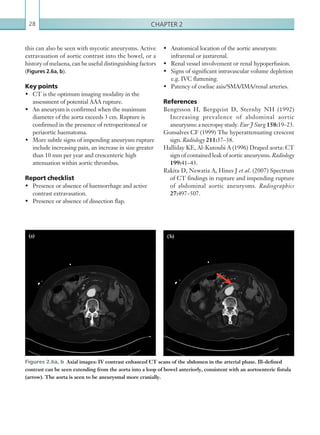

settings) can help identify free air and distinguish

between intra- and extraluminal gas.

The next consideration is the location and

distribution of air. The peritoneal cavity is divided

into supra- and inframesocolic compartments by the

transverse colon, and this distinction can be useful

in radiological differentiation of upper and lower GI

perforations. Subsequently, upper GI tract perforation